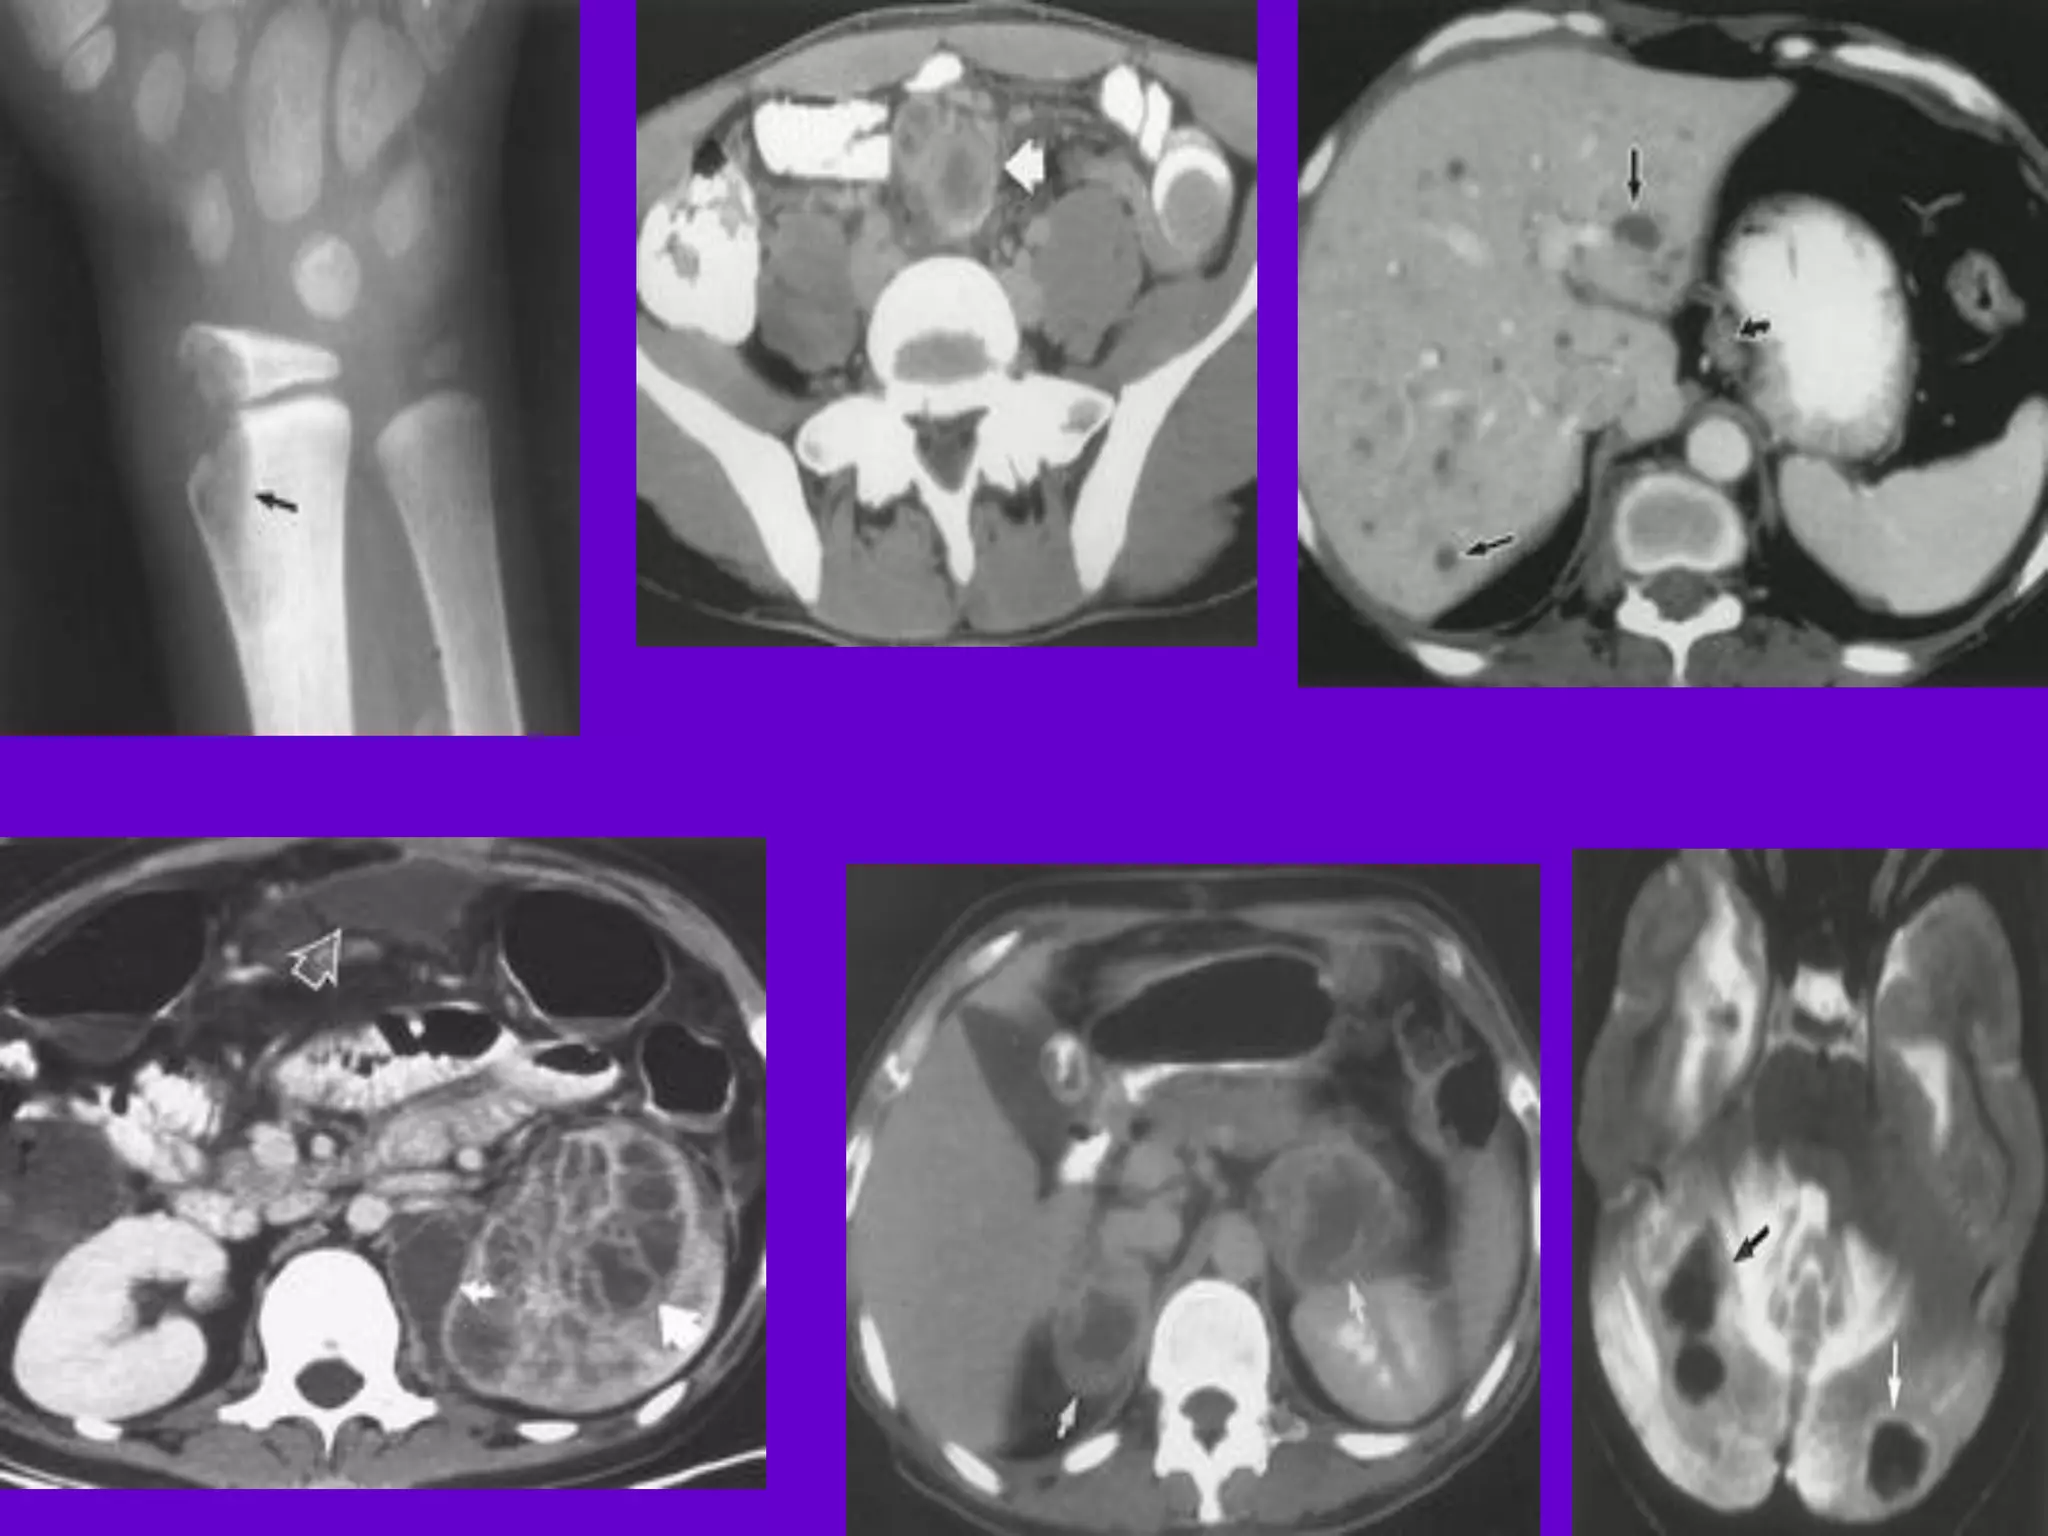

CT Scan and MRI Scan in the

diagnosis of TB

􀂄 The advent of CT and MRI imaging in

the last two

decades has redefined the approach in

analysis of

various diseases including TB.*

􀂄 CT and MRI have shown several

advantages over

conventional radiology in early diagnosis

and follow-up

of TB in different parts of the body.

*Buxi TBS Indian J Pediatr 2002;69:965-972

Pulmonary TB :

Lobar Pneumonia

􀂄

CT is superior than plain CXR in picking

up the

consolidation, atelectasis and the hilar LN

thereby

making the diagnosis easy.

􀂄 MRI reveals some of these changes,

however, CT is

the diagnostic modality of choice in such

cases.

Bronchopneumonia

On CT it is usually B/L and widespread,

not always

symmetrical involvement of lungs.

Hilar and Mediastinal

Lymphadenopathy

CT and MRI depict the hilar and

mediastinal LN

equally well.

􀂄 Calcification in the nodes is however

better seen on

CT.

􀂄 Necrosis is seen as focal areas of low

attenuation on

a CECT.

􀂄 On MRI focal necrosis is seen as areas

of increased

signal intensity on T2W images.

Skeletal TB

Pott’s Disease (vertebral TB)

CT and MRI helps in demonstrating a

small focus of

vertebral body involvement and defining

the extent of

the disease.

􀂄 CT/MRI help to evaluate TB involving

the craniovertebral

junction, sacro-iliac joint and posterior

appendages.

􀂄 They are also helpful in assessment of

spinal canal

encroachment , posterior element

involvement and in

deciding the surgical approach.

GIT TB

Strictures of the small bowel, mucosal

edema and

thickening are well visualized on CT.

􀂄 MRI depicts the para-aortic, aortocaval

and

mesentric lymph nodes effectively.

GUT TB 􀂄

Various patterns of hydronephrosis may

be seen

at MR urography.

􀂄 MRI helps to differentiate macronodular

TB

lesions from the other mass lesions.